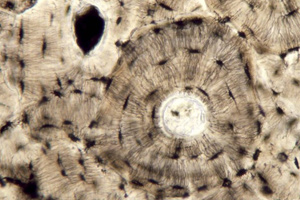

Material que replica tejido óseo

Su desarrollo y utilidad